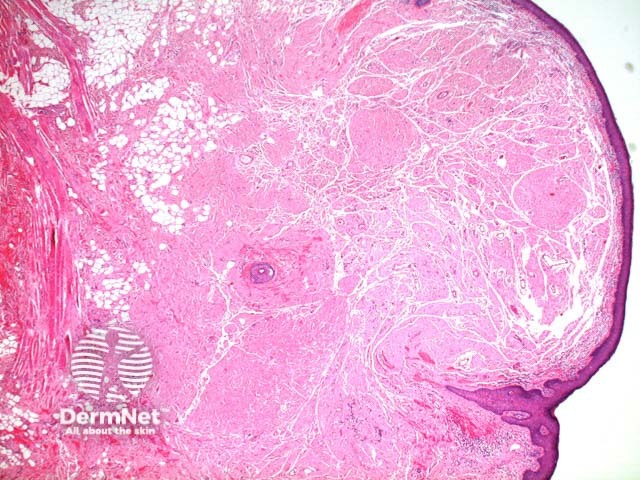

The scanning power view reveals a tumoral deposit within the dermis (figure 6). This may extend into the subcutaneous tissue (figures 7, 8, 9). Prominent clefting can be seen making superficial cases difficult to differentiate from colloid milium and paracolloid. The presence of numerous plasma cells in the accompanying inflammatory infiltrate, commonly with scattered Russell bodies, is helpful (figure 10).

Figure 6

Figure 7

Figure 8

Figure 9